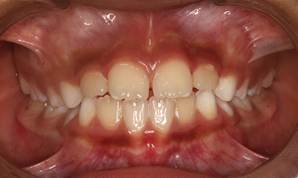

Análisis intraoral: Al observar la boca del paciente nos encontramos que la mucosa está húmeda y lubricada con pigmentación melánica, el frenillo es de inserción mucosa; hay poca inflamación de las encías. El paladar duro es profundo. El paciente está en dentición mixta, existe una mordida cruzada anterior con apiñamiento en el sector anteroinferior. En el arco superior se observa un diastema entre los incisivos centrales superiores permanentes, también se observa que estos dientes están ligeramente rotados. La relación molar de ambos lados es de clase III y la relación de los caninos deciduos también es de clase III.

Fig.3 Fotografía intraoral de frente Fig.

4 Fotografía intraoral de 45°

Fig. 5 Fotografía intraoral lado derecho Fig. 6 Fotografía intraoral lado izquierdo